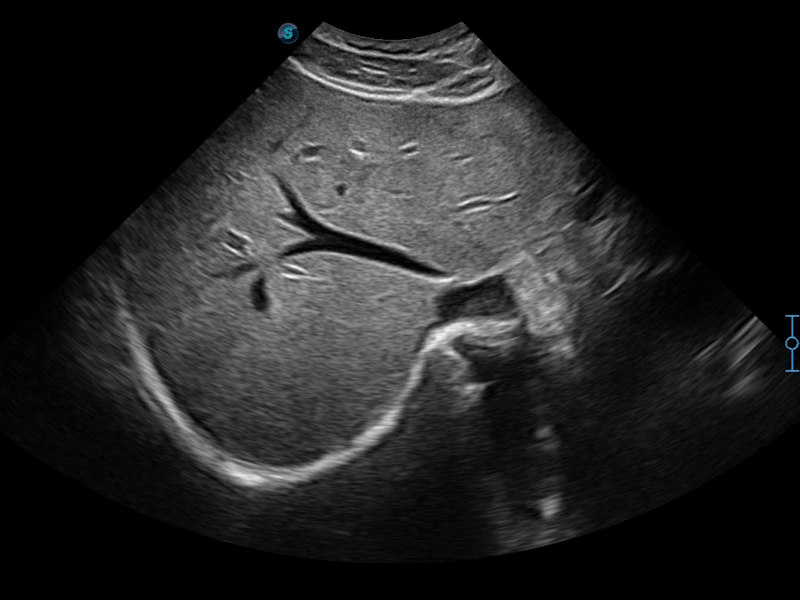

彩色多普勒超聲診斷系統(tǒng)

開(kāi)立醫(yī)療通過(guò)不斷的技術(shù)創(chuàng)新,為大眾的生命健康提供持續(xù)關(guān)愛(ài)。P12 Plus采用全新一代超聲成像平臺(tái),新平臺(tái)旨在將真實(shí)還原組織解剖結(jié)構(gòu)作為首要目標(biāo)。平臺(tái)采用全新集成化硬件模塊,搭載新一代芯片,系統(tǒng)性能得到大幅提升,為您的診斷提供了豐富的臨床信息。優(yōu)異的圖像表現(xiàn),豐富的探頭配置,全面的應(yīng)用功能,為您日常診斷提供了可靠的助手。